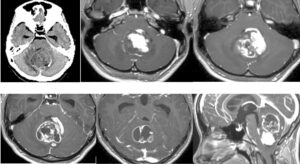

左海綿静脈洞内髄膜腫(複視)に対して、現在のスタンダードは放射線治療になりつつありますが、これも長期制御が困難なので、今回はBTOで左内頸動脈閉塞による血管内腫瘍塞栓を行う計画としました。それに先立ち、BTO時のStump <50mHgであったためSTA-MCAバイパスを行いました。